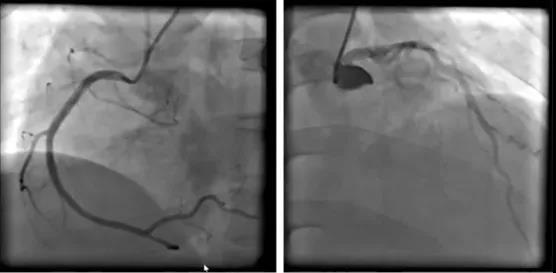

ECMO支持下冠脉造影显示右冠和左冠光滑,未见明显狭窄段(图3)。ECMO支持下主动脉造影可见胸主动脉、腹主动脉、双侧肾动脉、肠系膜上动脉均未见夹层或出血表现(图4)。

图3 ECMO支持下冠脉造影